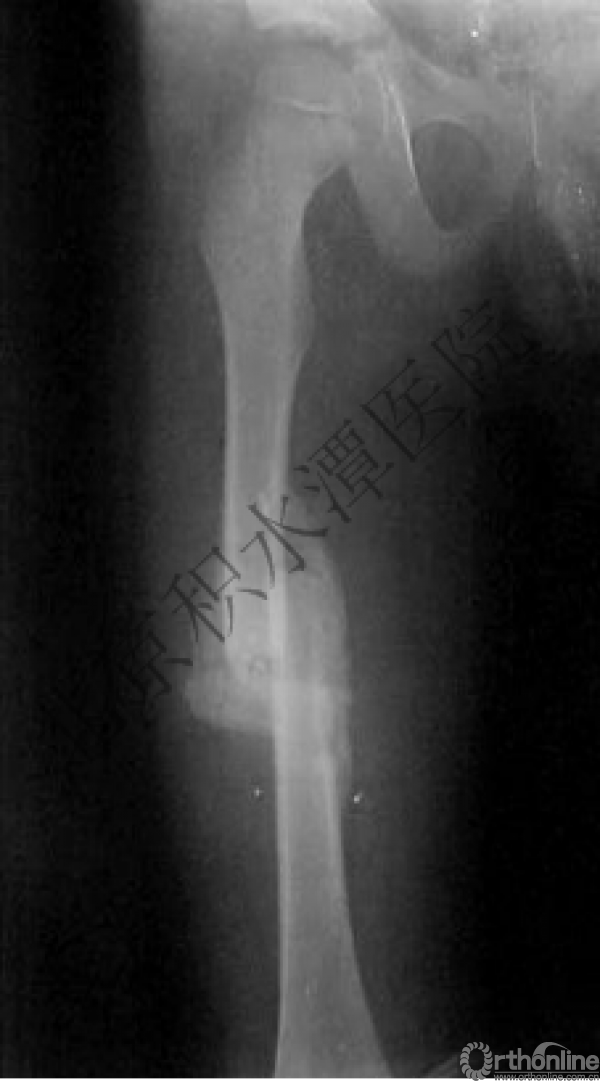

病例分享二

2岁、股骨干骨折,切开+内固定

简单牵引即可!为什么要如此大动干戈?

现实中又是怎样的呢?不知道这属于知识缺乏范畴还是道德品质问题?

匪夷所思!

新生儿股骨干骨折

为什么要手术治疗?

医源性损伤—不愈合!

不具备对儿童骨骼特点的基本了解,不了解儿童骨折的特点,想当然地治疗!